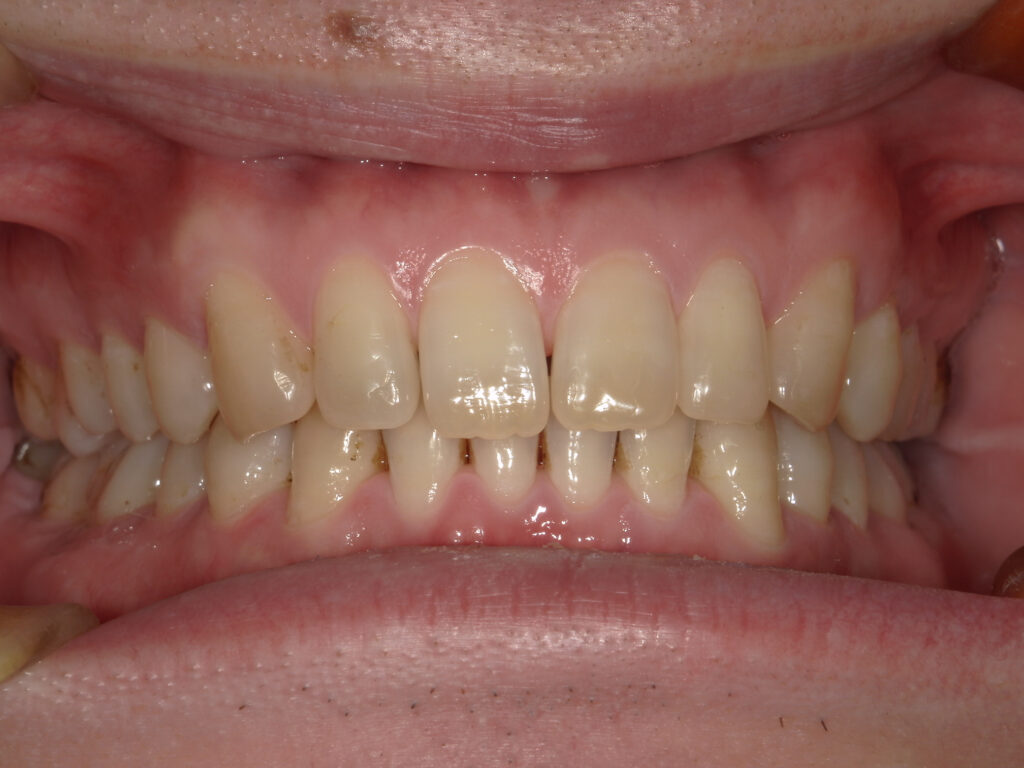

正面

治療後

患者様は上下の横の前歯の隙間を気にされており、「できれば完全に隙間を閉じたいが、ある程度改善されればよい」とのご希望で来院された。 インビザライン矯正では、前歯の近接移動を中心に計画し、効率的に隙間を閉鎖するため犬歯・小臼歯にアタッチメントを付与。また、閉鎖後の歯肉退縮やブラックトライアングルを最小限に抑えるため、歯根の平行性を意識して移動を行った。 治療により上下前歯の隙間は良好に閉鎖し、咬合も安定。審美的な改善とともに、発音や清掃性の向上にもつながった。 |